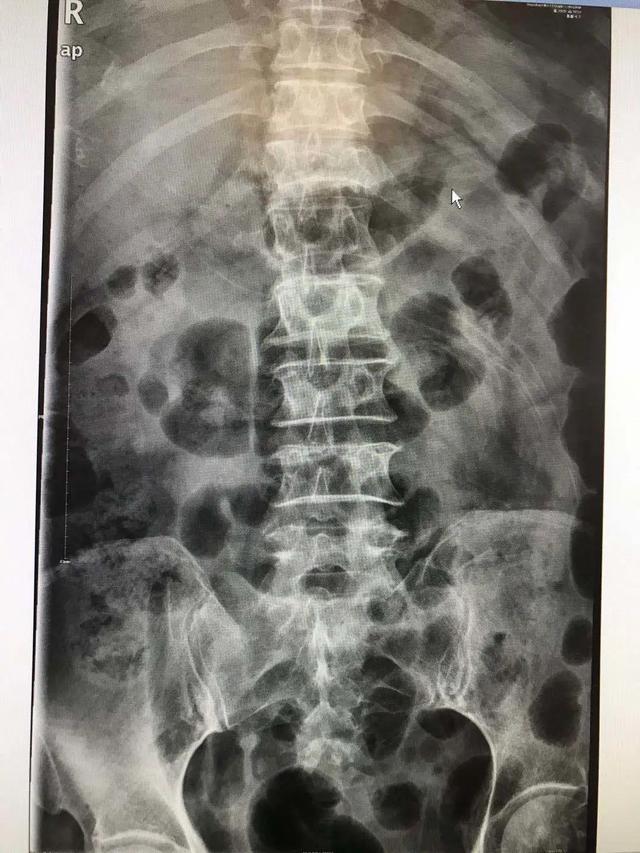

医生检查发现胡奶奶的胸椎、肋骨多处骨折,胸腔还有积液。